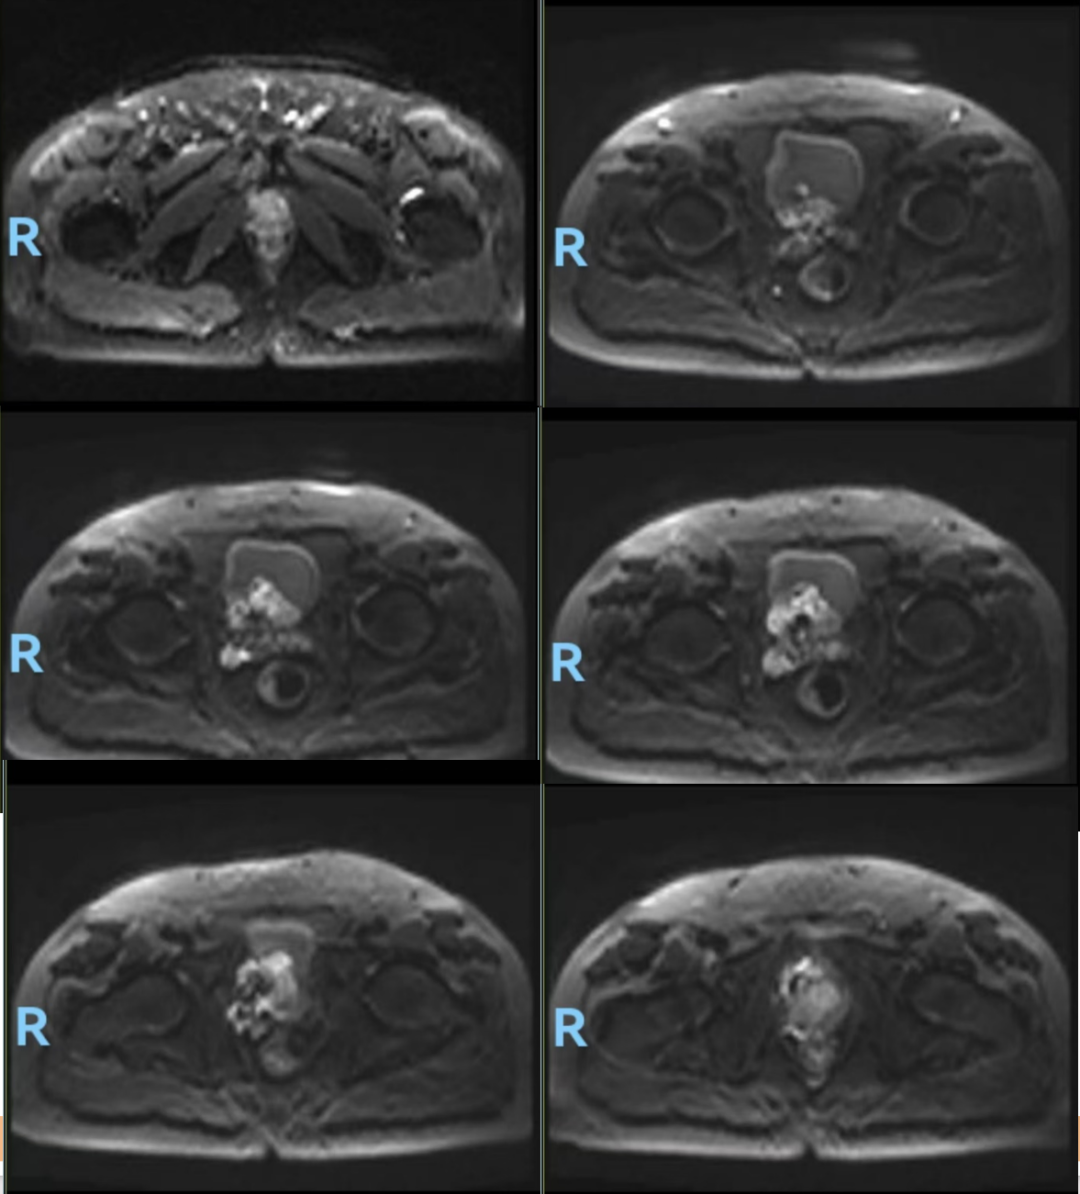

前列腺MR(图1,2024-04-18):1、考虑前列腺癌,PI-RADS 5,膀胱后壁、双侧精囊腺浸润;2、双侧耻骨及第1骶骨异常信号,转移瘤可能。

图1.前列腺MR(2024-04-18):前列腺体积不规则增大,约6.2cm(左右)x5.4cm(前后)x7.1cm(上下),中央带、外周带可见不规则片状短T2等T1信号灶,病灶向上突向膀胱,与膀胱后壁及精囊腺分界不清,DWI示病变呈弥散受限高信号,相应ADC信号减低。盆腔内见多个小淋巴结,较大者短径约为0.6cm。双侧耻骨及第1骶骨见稍长T1长T2信号,DWI弥散受限改变。直肠右侧壁局部增厚。诊断:1、考虑前列腺癌,PI-RADS 5,膀胱后壁、双侧精囊腺浸润;2、双侧耻骨及第1骶骨异常信号,转移瘤可能